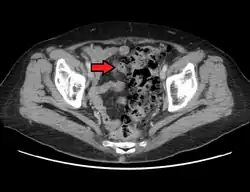

CT scan showing extensive diverticulosis of the sigmoid colon